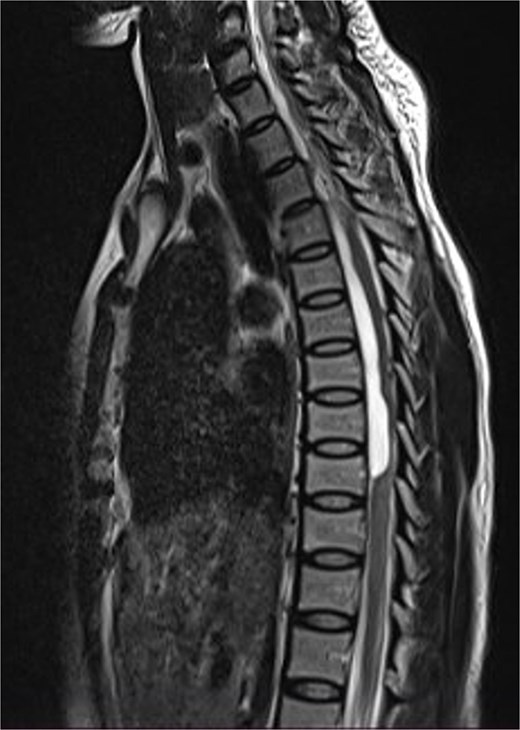

A 47-year-old man presented to us with progressive weakness of the extremities of 5 weeks duration. The weakness was first noticed in the left hand and progressed to involve the entire left upper limb and subsequently the right upper limb and the lower limbs. There was associated paraesthesia, constipation, and erectile dysfunction. Clinical examination revealed a middle-aged man with spastic quadriplegia and exaggerated muscle stretch reflexes. The sensory level was C4. Other systemic examination findings were normal. A clinical diagnosis of C4 non-traumatic myelopathy, Frankel B was made. Cervical spine MRI showed an intradural-extramedullary lesion with similar intensities to cerebrospinal fluid (CSF) on all sequences anterior to the spinal cord at C2–C4 with significant cord compression at C3–C4 and cord signal change on T2-weighted image at C2–C5 (Fig. 1). A diagnosis of cervical spine intradural AC was made. The lesion was accessed through C3–C4 laminectomies. At surgery, there was a cyst anterior to the cord with the latter flattened and displaced posteriorly. The cyst was excised completely and water tight dura closure done (Fig. 2). He made progressive post-operative neurological improvement and he was discharged on the 10th post-operative day. He was last seen 22 months post-surgery. At the time, he was ambulating without support, power was Grade 4+ to 5 in the upper and lower limbs.

Sagittal T1-weighted (a) and T2-weighted (b) cervical spine MRI images showing an intradural arachnoid cyst posteriorly displacing and compressing the spinal cord.

MRI is the imaging modality of choice for the diagnosis and follow-up of SACs [4]. It does not require intrathecal injection of contrast and demonstrates the location, size, extent, and nature of the cysts as well as neural elements compression and intrinsic cord changes among other features [7, 16–18]. On MRI SACs have similar signal intensities to those of CSF, hypointense on T1-weighted, and hyperintense on T2-weighted images [16]. Extradural cysts may show absent posterior epidural fat, epidural fat capping, and T2-hypointense cyst wall [16, 19, 20] (Figs 3 and 6b). Intradural cysts are characterized by widening of the subarachnoid space, displacement of the cord/cord compression and an undistinguishable cyst wall [2, 21] (Fig. 1). The site of communication between the cysts and subarachnoid may not be demonstrable on MRI [16]. Computed tomography myelograghy has been the imaging of choice in demonstrating the communicating site between the cyst and the subarachnoid cyst [16]. Newer MRI flow studies using cinematic MRI has proven to also be able to demonstrate the communication site [22].

(a) Sagittal T2-weighted cervical spine MRI image showing expanded subarachnoid space anterior to the spinal cord at C2–C4, posterior displacement and compression of the cord and cord signal change at C2–C5. The wall of the cyst is indistinguishable suggestive of intradural spinal arachnoid cyst. (b) Sagittal T2-weighted thoracic MRI image showing compression of the spinal cord anteriorly. There is visible hypointense cyst wall (arrow) suggestive of extradural cyst.